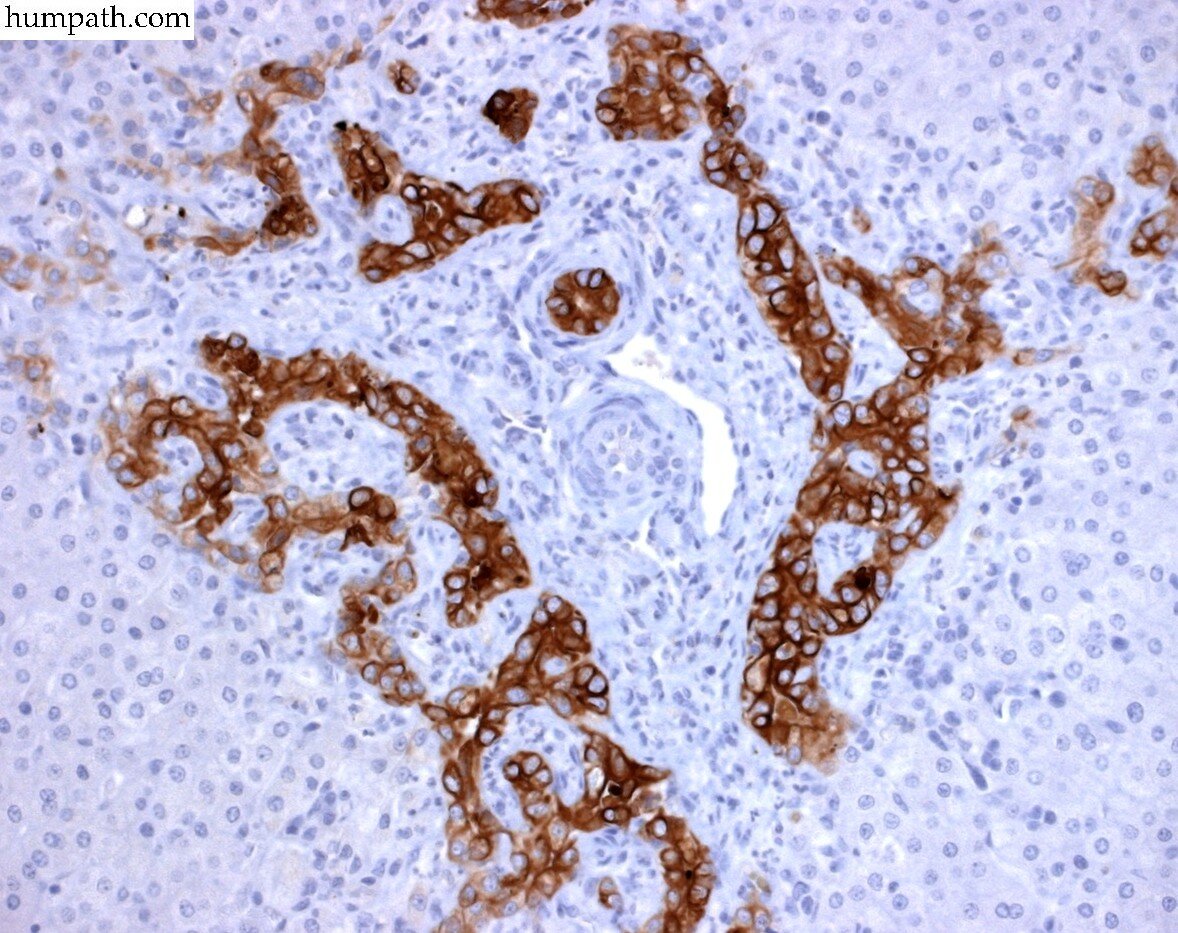

Definition: Increase in the number and prominence of small biliary channels in and around the portal tracts.

tubular to elongated profiles

lined by cuboidal or columnar epithelium

well-defined lumen or not